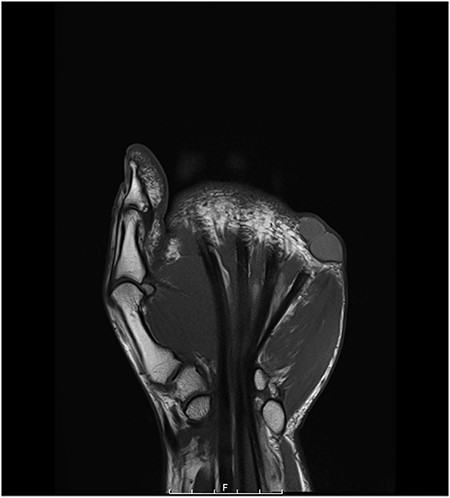

MRI findings showed a tri-lobed lesion (Figs 1 and 2) overlying the volar aspect of the base of the proximal phalanx of the left little finger—consistent with a complex ganglion cyst. The lesion was adjacent to but separate from the flexor sheath and the radial neurovascular bundle of the left finger. With malignancy in mind, chest X-ray did not reveal any associated lung lesion or nodularity and an ultrasound scan of the axilla did not elucidate any lymphadenopathy. Consequently, surgical excision of the lesion was performed and histological analysis conducted.

axial MRI scan of the left hand showing the DPC at the level of the fifth MCP joint.

coronal MRI scan of the left hand showing the DPC at the level of the fifth MCP joint.